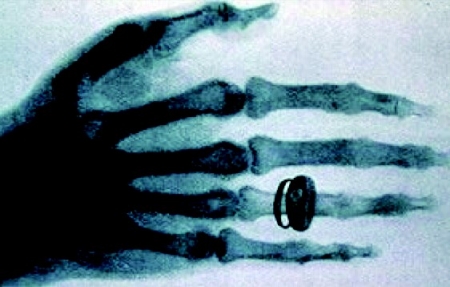

他一步测试,发现这是一种穿透性很强的电磁波射线。他把这种电磁波命名为X光,又叫X射线,“X”是无法了解的意思。X射线要被阻挡,关键由射线强度、频率、阻挡物质与射线作用程度、阻挡物质厚度、阻挡物质大小共同决定。当时伦琴要求他的妻子用手捂住照相底片。显影后,夫妻俩在底片上看见了手指骨头和结婚戒指的影像。